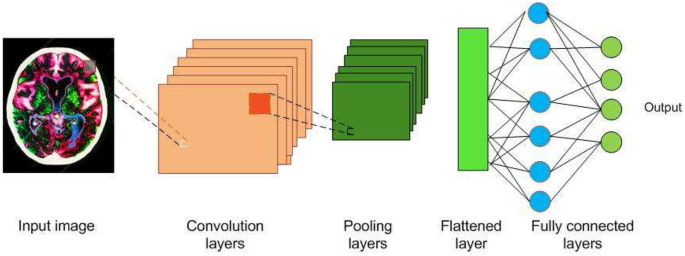

3 A brief introduction to CNNs

Image understanding by animals is a very fascinating process, and a very simple task for them. But for a machine, to understand an image, there are lot of hidden complexities during the process. What animals feel is the eyes capturing the image, which is processed by the neurons and sent to the brain for interpretation. CNN is a deep learning algorithm inspired by the visual cortex of animal brain [ 30 ] and aims to imitate the visual machinery of animals. CNNs represents a quantum leap in the field of image understanding, involving image classification, segmentation, localization, detection etc. The efficacy of CNNs in image understanding is the main reason of its abundant use. CNNs are made of convolutions having learnable weights and biases similar to neurons (nerve cells) of the animal. Convolutional layers, activation functions, pooling and fully-connected layers are the core building blocks of CNNs, as depicted in Fig. 1 . Very brief introduction to CNNs has been presented in this paper. Detailed discussions on CNNs are presented in [ 9 , 41 ].

3.1 Convolution layers (Conv layers)

The visual cortex of the animal brain is made of neuronal cells which extract features of the images. Each neuronal cell extracts different features, which help in image understanding. The conv layer is modeled over the neuronal cells and its objective is to extract features, such as edges, colors, texture and gradient orientation. Conv layers are made of learnable filters called convolutional filters, or kernels, of size \(n\times m\times d\) , where d is the depth of the image. During the forward pass, the kernels are convolved across the width and height of input volume and dot product is computed between the entries of the filter and the input. Intuitively, the CNN learns filters that gets activated when they come across edge, colors, texture etc. The output of the conv layer is fed into an activation function layer.

3.3 Pooling

Pooling layer performs a nonlinear down sampling of convolved feature. It decreases the computational power required to process the data through dimensionality reduction. It reduces the spatial size by aggregating data over space or feature type, controls overfitting and overcomes translation and rotational variance of images. Pooling operation results in partitioning of its input into a set of rectangle patches. Each patch gets replaced by a single value depending on the type of pooling selected. The different types are maximum pooling and average pooling.

3.4 Fully connected (FC) layer

FC layer is similar to artificial neural network, where each node has incoming connections from all the inputs and all the connections have weights associated with them. The output is sum of all the inputs multiplied by the corresponding weights. FC layer is followed by sigmoid activation function and performs the classifier job.